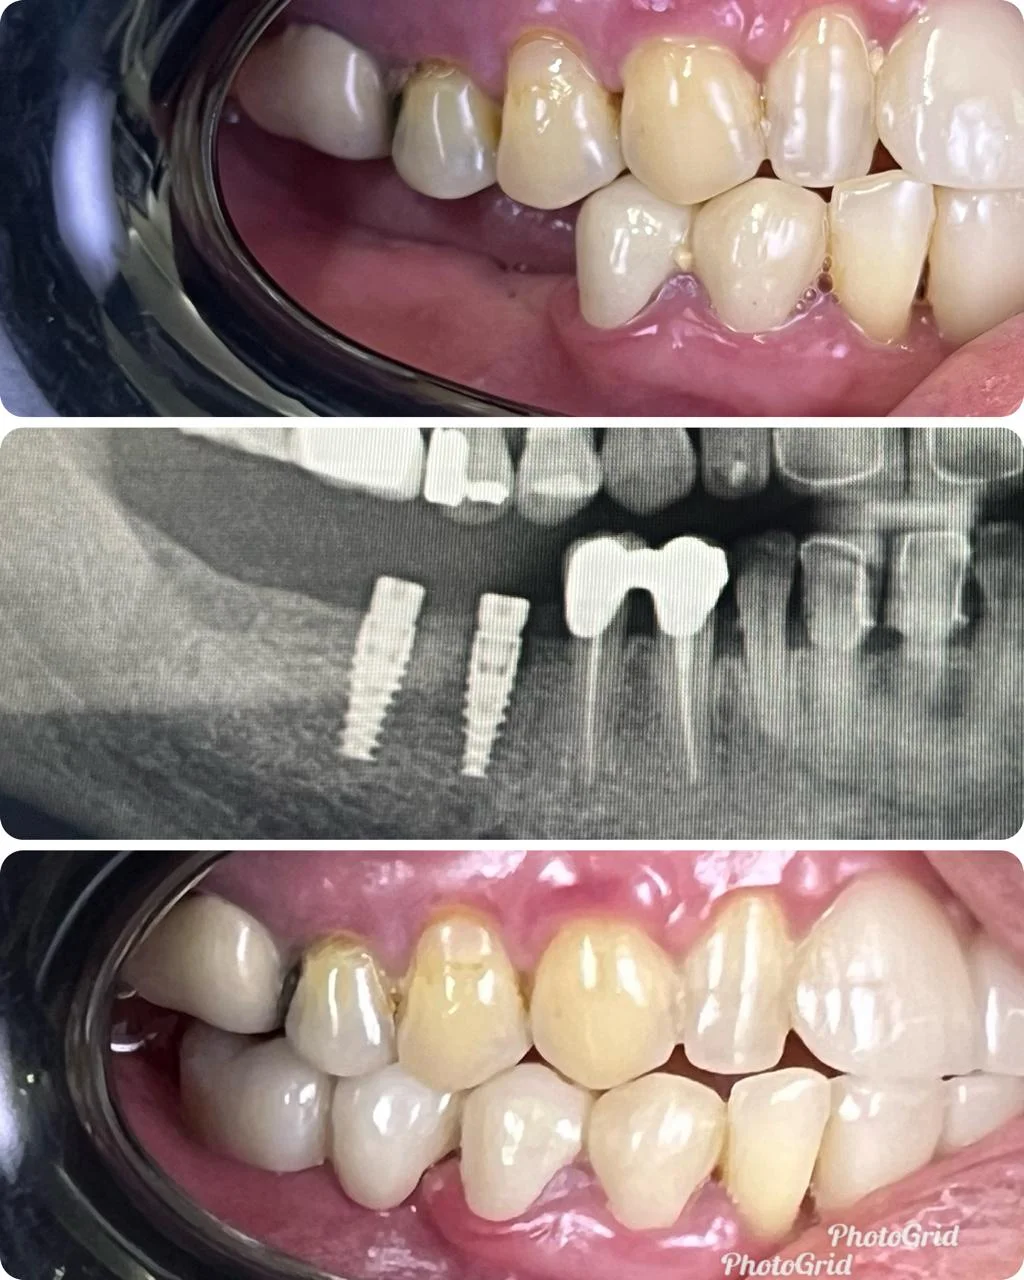

Showing Our Expertise In Dental Implantology